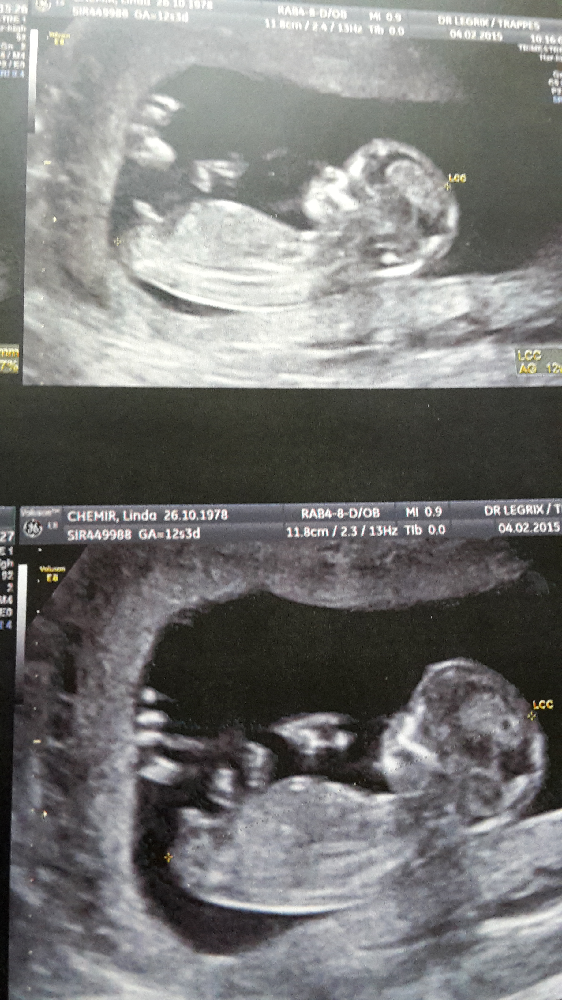

Echographie bebe 12 sa-J'ai eu mon écho à 12 SA et il m'a dit que du fait que le bourgeon soit en haut, il y a de forte chance que ce soit une fille Et je ne pense pas qu'il dirait ça juste pour le dire , je l'ai payé 130 euros, j'ai eu toutes les échos et j'espère vraiment que c'est une fille car d'un coté cela fait un mois que je me suis mise ça en tête/ Une datation précise de la grossesse Il est fondamental de connaître l'âge gestationnel sans ambiguïté pour le suivi de ces grossesses à risque de prématurité et RCIU Les critères de datation sont les mêmes que pour les grossesses uniques (longueur craniocaudale de 7SA à 12 SA et diamètre bipariétal après 12 SA)

A 14 SA (semaines d'aménorrhée), soit 12 semaines de grossesse effective, c'est bientôt la fin de votre troisième mois de grossesse Votre corps continue de changer, notamment la poitrine et surtout le ventre qui s'arrondit Bébé poursuit quant à lui sa croissance, ses organes sont désormais opérationnels C'est aussi le moment d'envoyer votre déclaration de grossesse Tableau de biométrie foetale DISTANCE CRANIO CAUDALE (TETE FESSES ) EN MILLIMETRES à 5 semaines d'aménorrhée 1 à 2 mm à 7 semaines d'aménorrhée 8 mm à 9 semaines d'aménorrhée 25 mm à 10 semaines d'aménorrhée 33 mm à 11 semaines d'aménorrhée 43 mm à 12 semaines d'aménorrhée 55 mm à 13 semaines d'aménorrhée 68 mm à 14 Votre commentaire date un peu mais je suis dans la même situation que vous a l inverse j ai 3 garcons et 1 fille et je suis enceinte de mon 5ème bébédepuis lapremiere écho la gynéco m a dit que c était encore un garconje suis à 22 sa je vais avoirmon écho morpho la semaine prochaine mais depuis 12 sa je suis déçue de savoir

Maman d'une adolescente en pleine puberté, d'une petite puce de 5 ans et d'un petit bonhomme de 6 mois, je suis une vraie pile électrique Faut que ça bouge tout le temps !Vous devriez tout de même passer une autre échographie entre 18 et 22 semaines de grossesse afin de fournir encore plus de détails sur la morphologie de votre bébé La première échographie montrera également si vous attendez un bébé, des jumeaux ou plus Il est toujours utile de savoir, le plus tôt possible, s'il s'agit d Echo 12 SA 3 jours le 27/07 bébé mesure 63cm et son coeur bat à 153p/m 80% de chances que tu sois une petite princesse On t'aime !